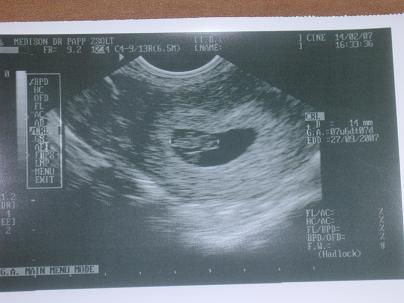

Kisnyuszim:

Kép

Dobogott a szivecskéje.

Uh szerint kissebb, 7+6 v. 8+0.

De ugye hőmérőztem és aszerint is 5. nappal később fogant, szval így reális.

A szülési időt hagytuk szept. 22-n.

Csajok, olyan boldog vagyok. )))))